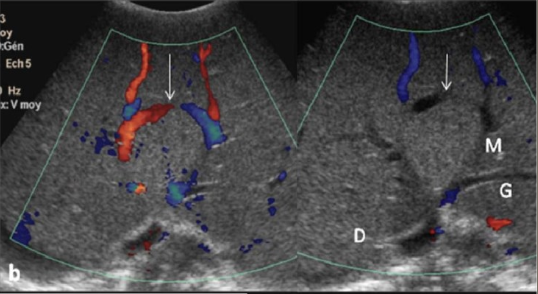

2D US: intraluminal material isoechoic to liver, hepatomegaly, splenomegaly, ascites, edema

color doppler: no communication between hepatic vein and IVC

DDX: IVC thrombosis (reduced/absent venous flow, but no hepatic vein occlusion), portal vein thrombosis (same secondary findings, but echogenic material in lumen of PV)